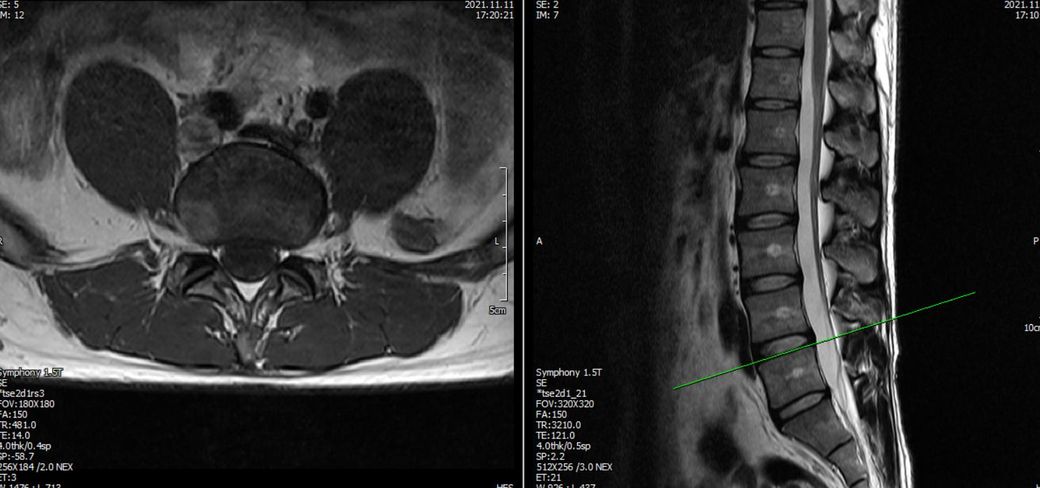

21년도와 24년도 각각 찍은 L spine 사진입니다.

2021년 영상